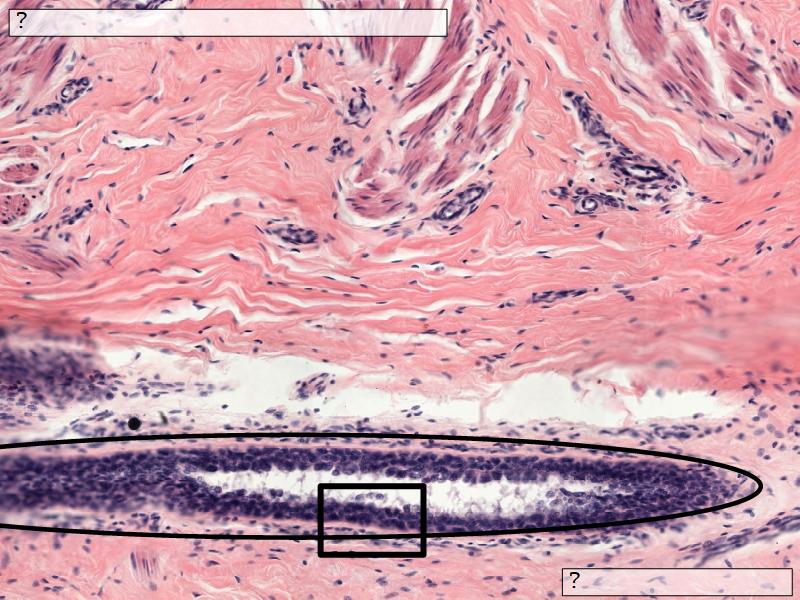

- Covered with skin

- Consists of dense collagenous connective tissue

- Interlaced with smooth muscle fibres

- Contains openings of lactiferous ducts

Skin

- Keratinized stratified squamous epithelium

- Lactiferous sinusses

- Stratified cuboidal epithelium